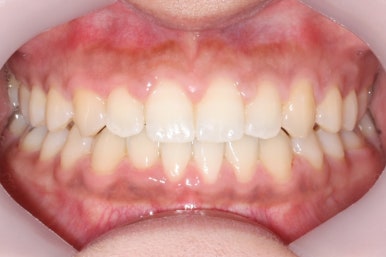

부산치아교정치과에서 치료한 이 사이가 벌어진 틈새교정을 마무리 했을 때의 모습을 보여드리겠습니다.

몰라보게 바뀌었습니다.

틈새가 다 모였고 다시 틈이 벌어지지 말라고 앞니 안쪽에는 유지장치를 달고 마무리를 했습니다.

전후를 비교해 보겠습니다.

부산치아교정치과 전후 모습입니다.

변화가 놀랍습니다.